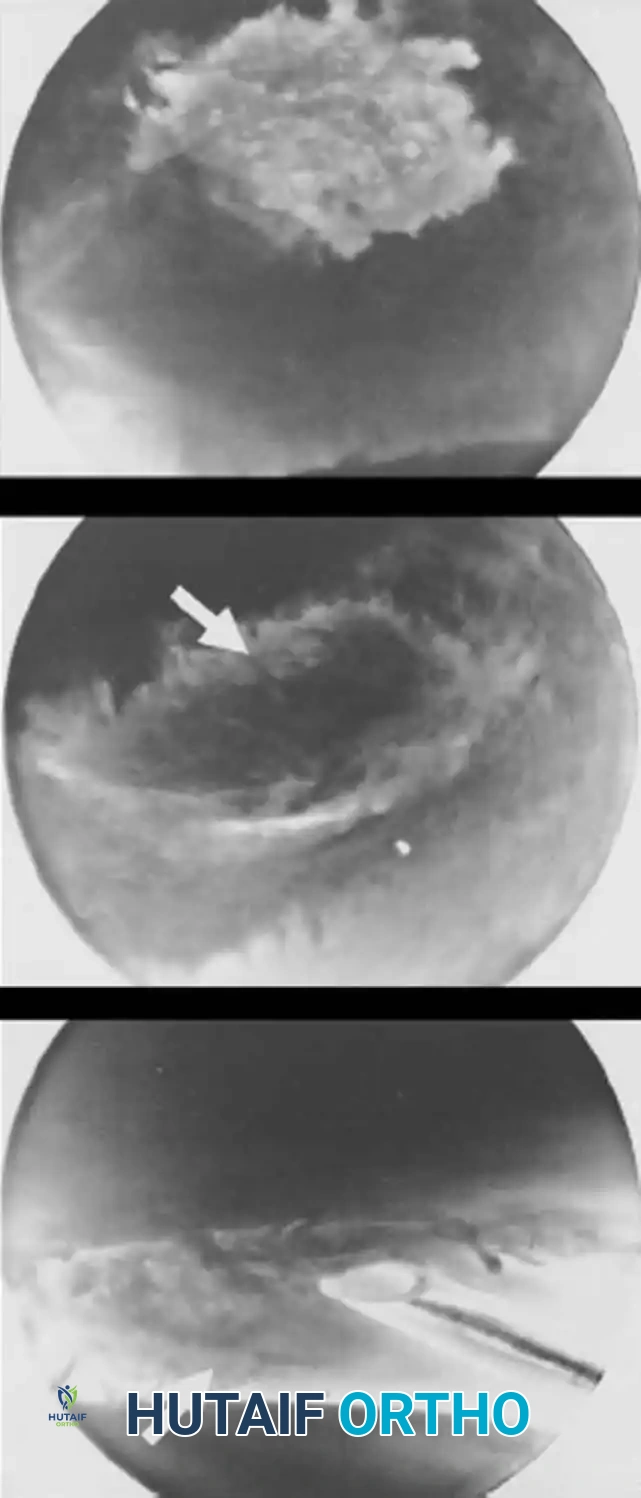

Surgical Technique: Arthroscopic Debridement of TFCC Tears (Class 1A)

Class 1A lesions occur in the avascular central portion of the disc. Because they lack healing potential, the treatment of choice for symptomatic tears is arthroscopic debridement.

Surgical Warning: When debriding a central TFCC tear, never excise more than two-thirds of the central disc. A minimum of 2 mm of the peripheral rim must be preserved to maintain the integrity of the radioulnar ligaments and prevent iatrogenic DRUJ instability.

Step-by-Step Procedure:

1. Setup and Portals: Suspend the wrist with 10 to 15 lbs of traction. Establish the 3-4 portal for the arthroscope and the 6R portal for instrumentation.

2. Diagnostic Tour: Evaluate the radiocarpal joint. Clear synovitis using a 2.0 mm or 2.9 mm full-radius shaver.

3. Assessment: Probe the central TFCC tear. Assess the trampoline effect; a loss of tension indicates a peripheral tear.

4. Debridement: Introduce a punch or shaver through the 6R portal. Carefully resect the unstable flap of the central perforation. Smooth the edges to prevent mechanical catching.

5. Closure: Close portals with non-absorbable sutures and apply a volar splint.